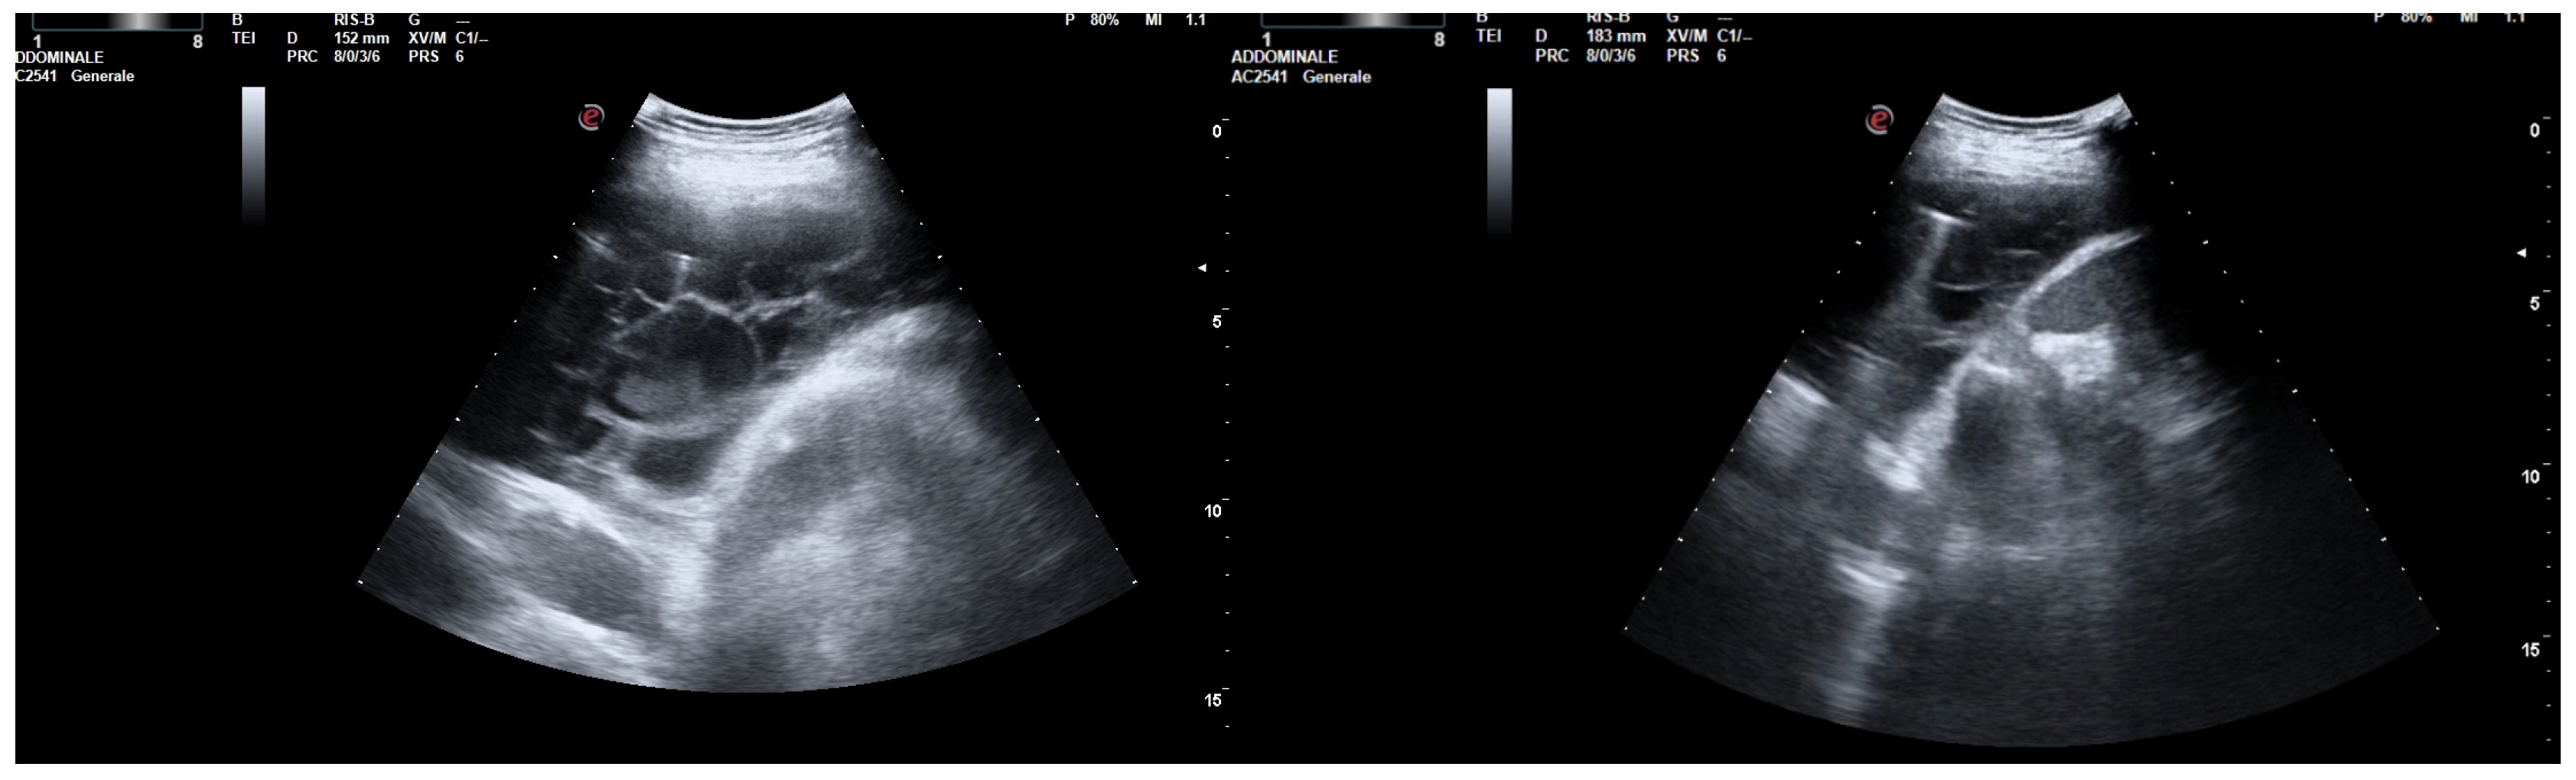

Immediately following the instillation of the fibrinolytic agent, the chest drain was clamped for approximately 4 h. Then, irrigation with a few ml of saline solution was performed, and the chest tube was reopened. US observations 24 h after the intrapleural fibrinolysis showed a marked reduction in the extent of the effusion and localizations (Figure 3). After 72 h, the remaining fibrin sprouts had completely disappeared (Figure 3). This facilitated the drainage of the remaining exudate. At the same time, there was an improvement in his clinical condition with the disappearance of his fever and the restoration of normal oxygenation, which led to the discontinuation of oxygen therapy.

Figure 3. Chest US 48 h (left) and 72 h (right) after intrapleural instillation of urokinase.